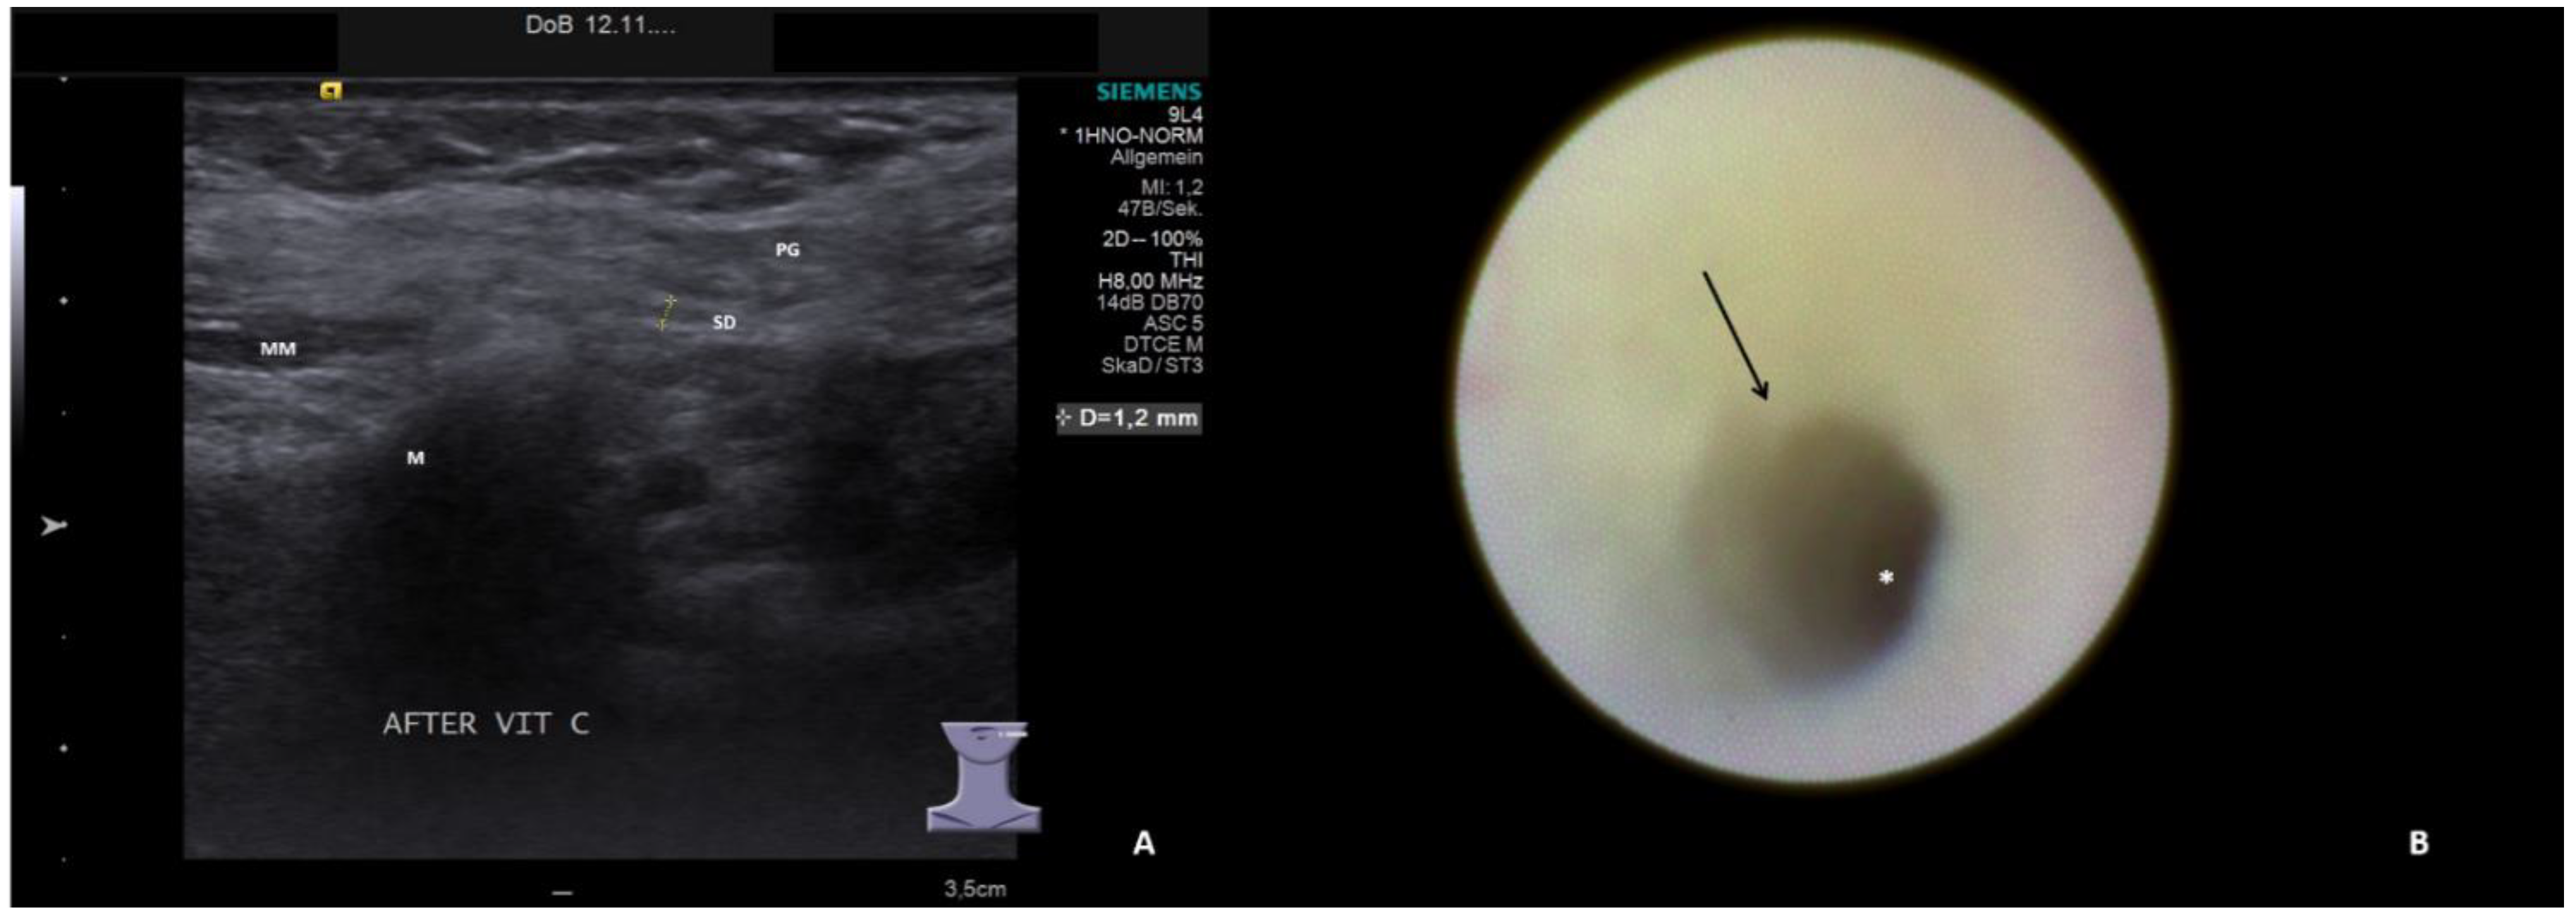

- Hypoechoic and homogeneous (no relevant loss of gland parenchyma; Figure 1A)

- Chronic sialodochitis (SD: inflammation, paleness of the duct wall, plaques, discharge; Figure 1B; Supplementary Video S1)